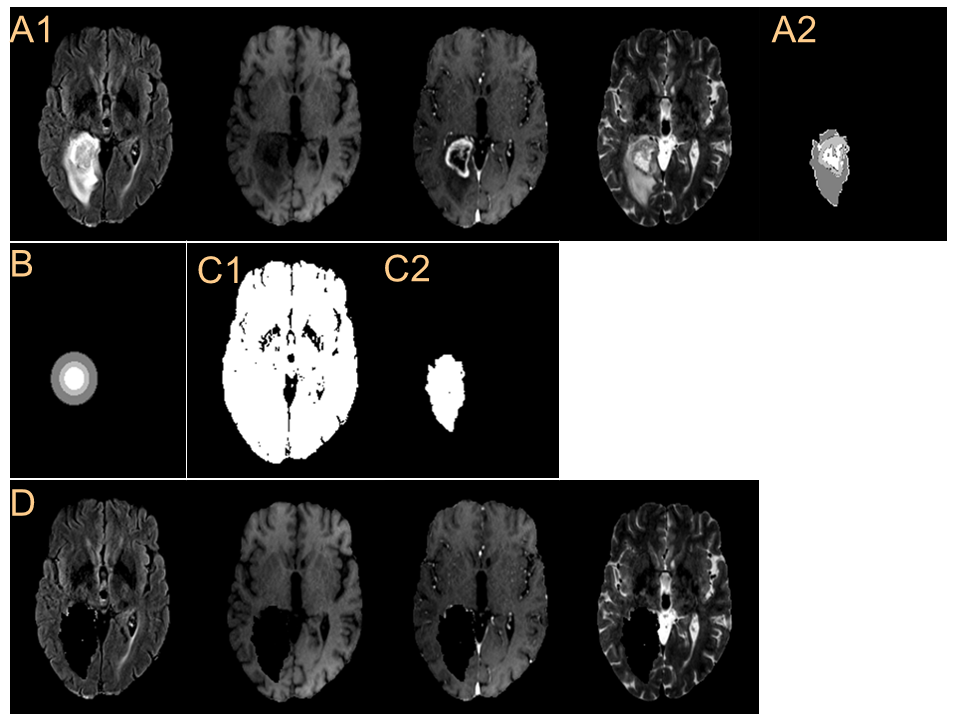

Refer to caption

Figure 6: Synthesized brain tumor images, X^Tsubscript^X𝑇\hat{\textbf{X}}_{T}, from various normal brain images, XNsubscriptX𝑁\textbf{X}_{N}, with given concentric circles, c𝑐c. (A) Given concentric circles and (B1-B4) various multi-contrast normal brain images, XNsubscriptX𝑁\textbf{X}_{N}. (C1-C4) m^gradesubscript^𝑚𝑔𝑟𝑎𝑑𝑒\hat{m}_{grade} generated from the given concentric circles for various normal brain images. (D) Synthesized multi-contrast brain tumor images, X^Tsubscript^X𝑇\hat{\textbf{X}}_{T}.

As shown in Fig.6(A, B1-B4), only one example of concentric circles is combined with various normal brain images, XNsubscriptX𝑁\textbf{X}_{N}, as input of the proposed network. Various m^gradesubscript^𝑚𝑔𝑟𝑎𝑑𝑒\hat{m}_{grade} in Fig.6(C1-C4) are generated depending on normal brain images while the same concentric circles are applied. In addition, the synthesized results, X^Tsubscript^X𝑇\hat{\textbf{X}}_{T}, show how the normal brain images affect the tumor-part images as shown in Fig.6(D1-D4).